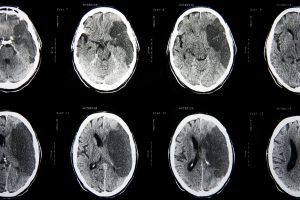

Тархины зарим хэсэгт цусан хангамж дутагдсанаас бие махбодын үйл ажиллагаа өөрчлөгдөх, алдагдахыг харвалт гэдэг. Харвалтад 45-аас дээш насныхан илүү өртөмтгий байх бөгөөд энэ нас ахих тусам тархинд цус харвах эрсдэл хоёр дахин нэмэгддэг байна. Түүнчлэн тарган, архи тамхи хэргэлдэг, чихрийн шижин өвчинтэй, халуунд ажилладаг хүмүүс цус харвалтад илүүтэй өртдөг ажээ.

Таних шинж тэмдэг

- Нүүр муруйх

- Гар унжих

- Хэл, яриа ээдрэх

- Тэнцвэр алдах, гуйвах /Тархины цочмог харвалтын эмзүйн удирдамж 2013 он/